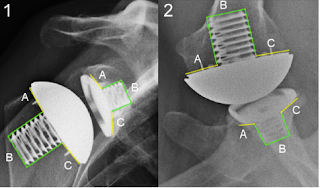

Note in these two year followup films the preservation of the humeral bone stock, the stable fixation of the long stem achieved with impaction autografting, and the absence of stress shielding/bone resorption.

Note also the absence of radiolucent lines around the all polyethylene glenoid component, the absence of cement on the back side of the glenoid component, and the bone ingrowth between the flanges of the central peg of the glenoid component (arrow).

On the postoperative 'truth' axillary view, note again the bone ingrowth, the absence of back side cement, and the absence of radiolucent lines as well as the centering of the humeral head in the glenoid and the preservation of glenoid bone stock.